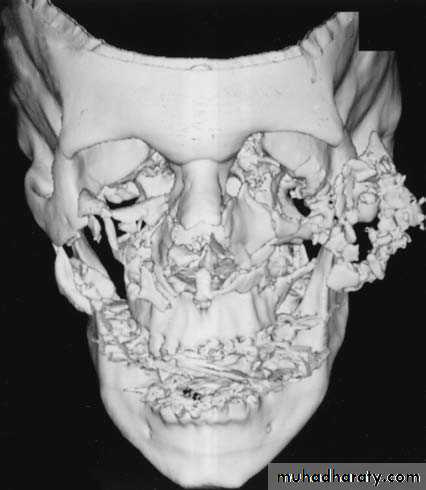

* Panfacial fractures are those involving the mandible, maxilla, and zygomatic complex at the same time and usually accompanying naso-orbito-ethmoid (NOE) and frontal bone fractures.

* They are often associated with soft tissue injuries and loss of bony structures that can lead to severe posttraumatic deformities and disabilities like malocclusion, “dish” face deformity, and enophthalmos

• The fractures are usually extensively comminuted.• Always compound and contaminated.